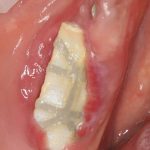

Устанавливаем формирователи десневой манжеты. Сегодня я называю эту процедуру не менее важной, чем любой другой этап имплантологического лечения:

И швы. Просто швы. Никаких дополнительных процедур.

Если честно, то сейчас бы я использовал другой шовный материал и другой тип швов. Одно неизменно, — и я об этом много раз говорил, — самая широкая часть формирователя десны должна находиться на уровне десны. Так, чтобы эффективно отрабатывать т. н. «биологическую ширину».

Через неделю я снял швы, а мой коллега Андрей Карнеев (дело было еще в НИЦ) приступил к изготовлению протезов. На это ушло полторы недели: